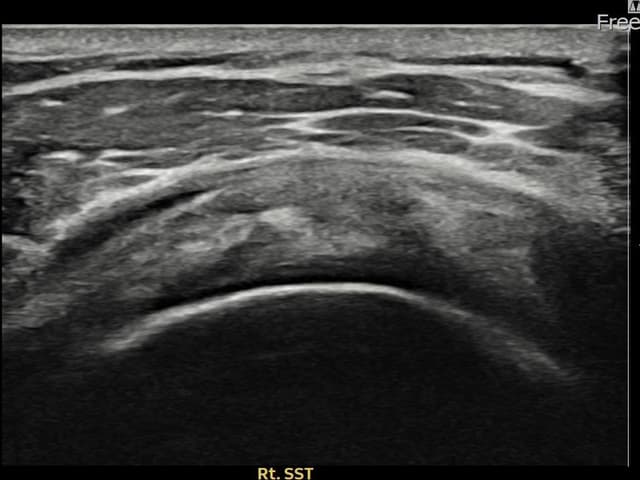

[촬영시기:22.09.19~22.12.09]

[어깨인대 축소봉합술] 우측 어깨 통증이 수개월간 지속되어 내원하셨습니다.